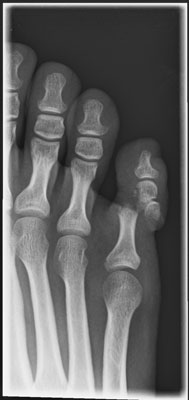

Update zu meiner Verletzung hinter dem ominösen Video:

Das war passiert:

http://www.mrufer.ch/motorrad/forum_linked/zeh_hhm.jpg

Der Zeh kam entgegen ersten Aussagen wieder gut und ich kann inzwischen halbwegs normal gehen. Alles was mit Laufen/Rennen/Fuss biegen zusammen hängt, hat mir die Ärtzin allerdings noch für weitere 2-3 Monate verboten, weil der Knochen aufgrund des wüsten Bruchs noch zeit braucht.

Fazit: Noch mal glück gehabt. Dass der Zeh wieder gut kam, ist nicht selbstverständlich. Mir bleibt der Dank an die Ärzte!